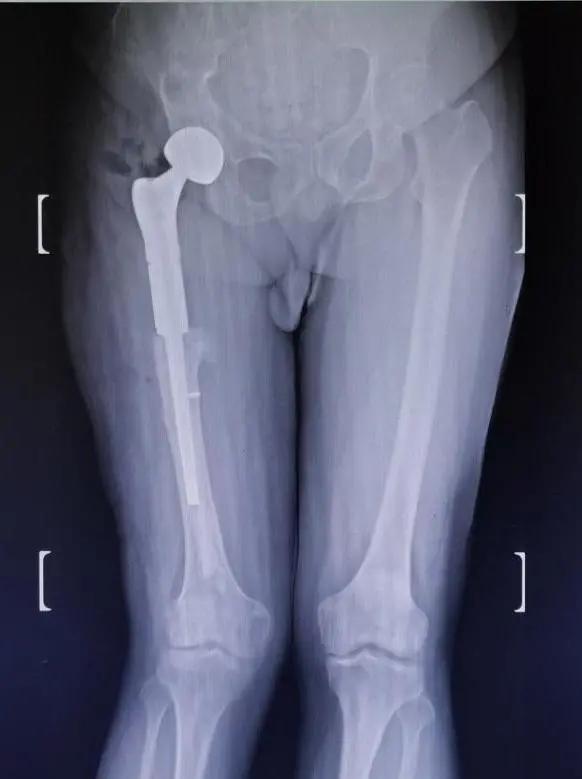

针对如此棘手的病例,且上海市血源非常紧张的情况下,郑龙坡教授团队经过充分的术前规划并与家属仔细沟通,决定分期对患者进行手术,一期对肱骨头骨折、肩关节脱位进行手术,二期采取肿瘤型假体置换的方式解决股骨颈骨折、股骨近端骨纤维结构不良伴严重畸形、股骨中段骨不连、内固定断裂等问题。

按照预定计划,患者一期进行了肩部的手术,手术及术后康复锻炼非常顺利。二期股骨手术,先把原来断裂的内固定物取出,再把畸形愈合的股骨近端从骨不连的地方切除,同时切除周围大量增生的骨痂,安装定制的人工股骨近端假体,并重建周围软组织平衡,历经2个小时的奋战,手术顺利完成。

先后两期手术都未予输血,不仅把几处骨折问题解决了,还把吴先生多年的老残一并给矫正了,通过植入的人工假体,左右腿长短已经相差无几,且没有之前担心的血管、神经损伤等并发症发生。术后在医护人员的细心呵护下,吴先生重新站立起来,告别了五十年跛行岁月,仍在康复中的他重新找回了自信,活出了精气神。